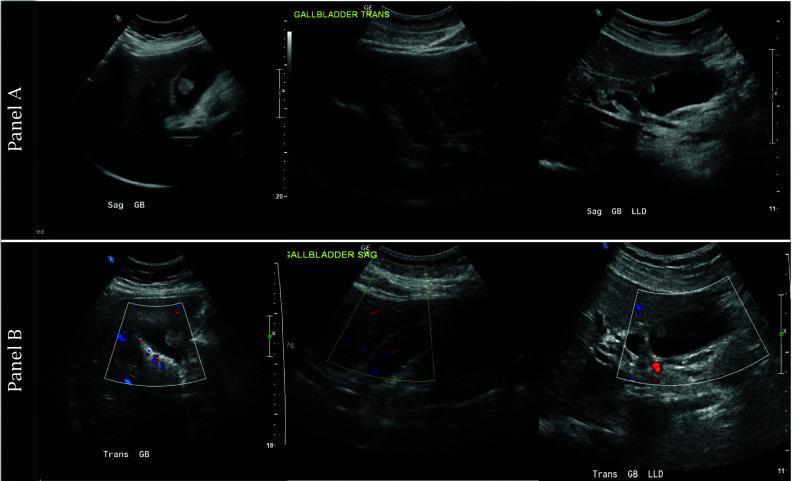

Polyps are reported on 1-10% of routine transabdominal ultrasound studies of the gallbladder. Prior studies have reported poor sensitivity and specificity for this diagnostic modality at determining malignant potential of polyps. The aim of this study is to determine the incidence of gallbladder polyps documented on ultrasound at a community hospital, evaluate the congruency of ultrasound with final histopathology, and explore factors which may improve ultrasound accuracy at diagnosing true adenomatous polyps.

We conducted a 5-year retrospective cohort study of patients undergoing cholecystectomy at Danbury Hospital between 2014 and 2019, identifying those with a pre-operative ultrasound mention of a "polyp" or "mass." We assessed the congruency of ultrasound findings with pathology reports.

Of the 2,549 cholecystectomies performed, 1,944 (76%) had pre-operative ultrasounds. Of those, 98 (5.0%) reported a polyp, measuring an average of 8.1 mm (SD 7.1 mm). Three (3.1%) specimens were identified as adenomas on final histopathology; the majority were benign pathologies including cholesterol polyp (18), cholesterolosis (20), adenomyoma (4), adenomyomatosis (7), and chronic or acute cholecystitis (44). Interestingly, only 1 of the 3 adenomas measured > 10 mm on ultrasound, the accepted indication for surgical resection.

The accuracy of transabdominal ultrasound in diagnosing true polyps is poor, with only 3% of polyps identified as adenomas based on pathology. Surgeons should use caution when making clinical decisions based on polyps identified on ultrasound, and more stringent diagnostic criteria are needed in order to decrease the false positive rate for diagnosis and screening.